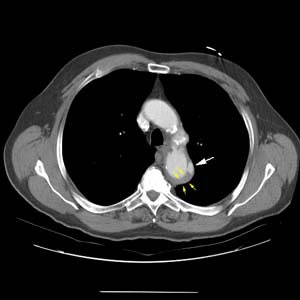

Intramural hematoma with penetrating ulcer:

This elderly patient presented with severe chest pain radiating to the back. The CT scan revealed a penetrating aortic ulcer (white arrow) arising from the lateral aspect of the distal aortic arch. Smooth high density mural thickening of the aortic wall (yellow arrows) can be seen and is consistent with an intramural hematoma.